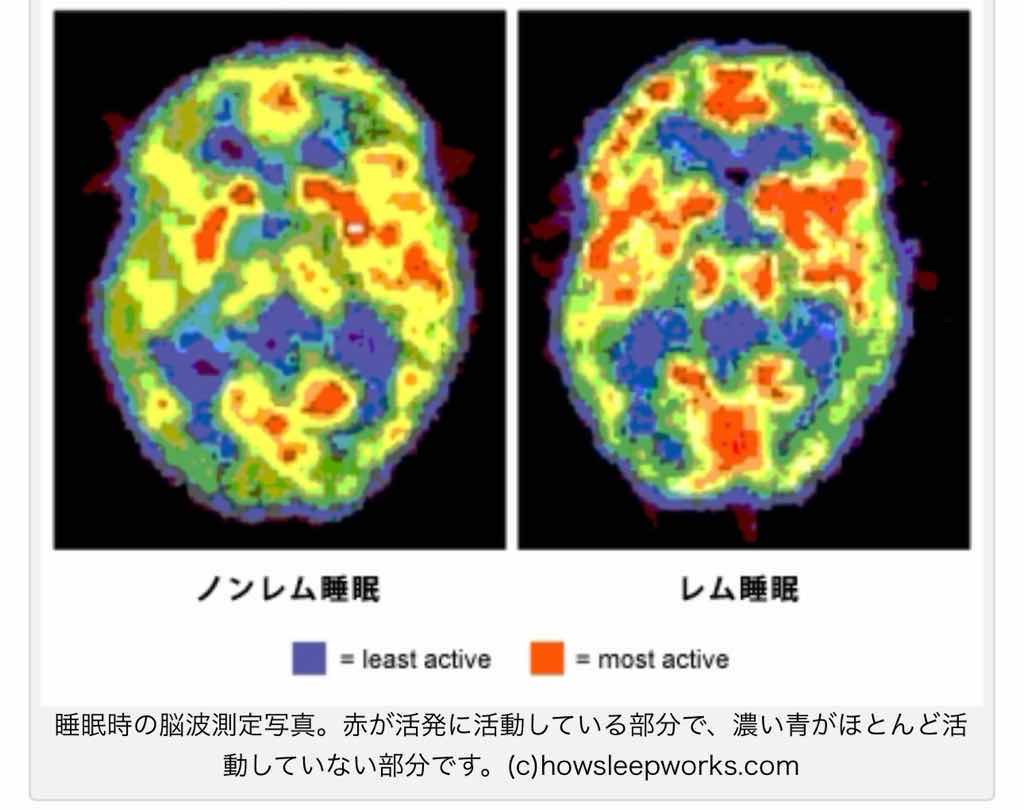

寝てる時

活発に動く脳https://stretchpole-blog.com/non-rem-sleep-1654